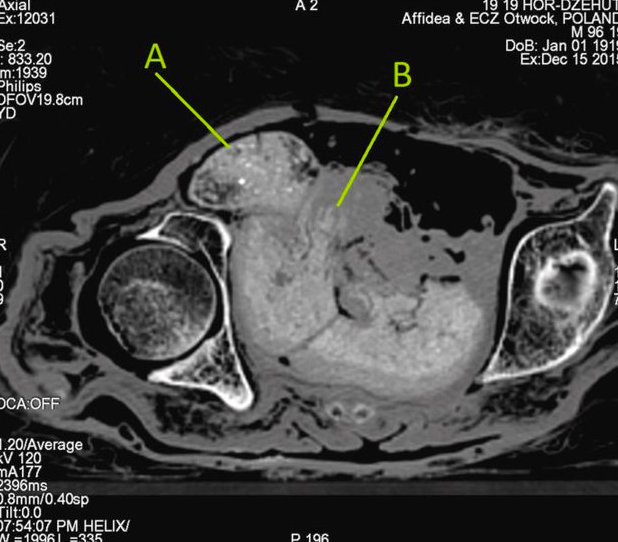

Буквой А на КТ плода обозначена голова зародыша, буквой В – рука Фото: Warsaw Mummy Project